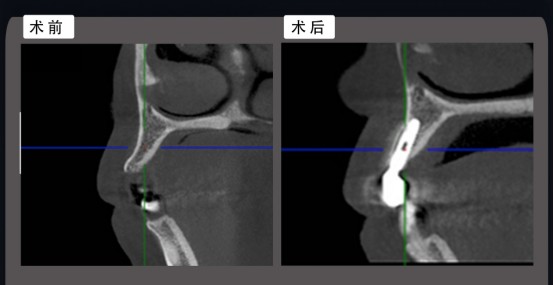

术前设计:

在与患者充分沟通后,我以微创和美学为导向进行了术前设计。尖牙区骨量充足,满足种植条件,重新设计了修复形态和位置。

2. 根据ITI指南种植体三维位置要求,我们选用了安卓健Axiom® 2.8窄直径种植体。